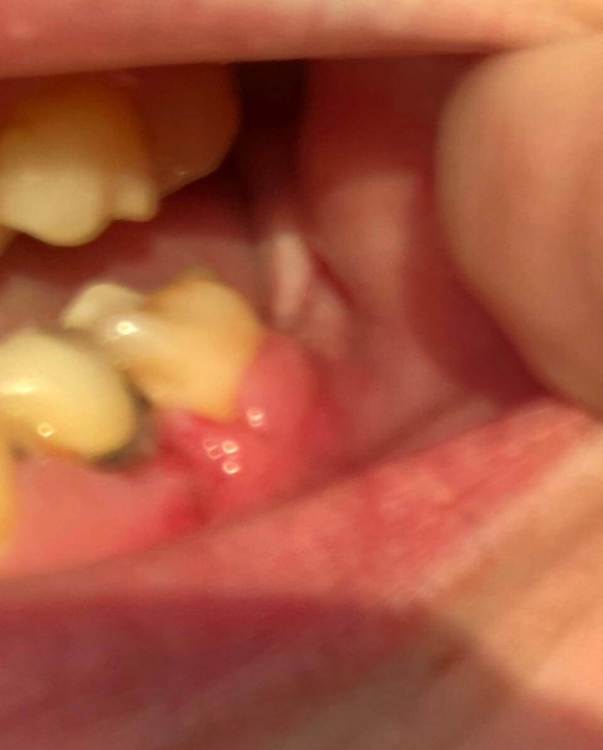

Здравствуйте ! Ситуация следующая - 6 сверху коронка с резекцией , долгое время осталась без антагониста , соотвественно выдвинулась (это уже мое предположение) . Чтобы спасти зуб , доктор принял решение повести гемисекцию корня . После - осталась рассечена десна .. Доктор говорит десна заживет , но визуал мягко говоря напрягает , так как при улыбке у меня это все видно ..

Фото 7,8 - Также была проведена резекция кисты 5 зуба снизу , с коронкой , и установка 7 импланта в качестве антагониста верхней 7 . Одной операцией . Коронка оголилась , швы сняли на 3 день .. доктор также утверждает что в дальнейшем будет все хорошо , зарастет . Также очень смешает внешний вид десны , десна стала волной даже на 6 ..